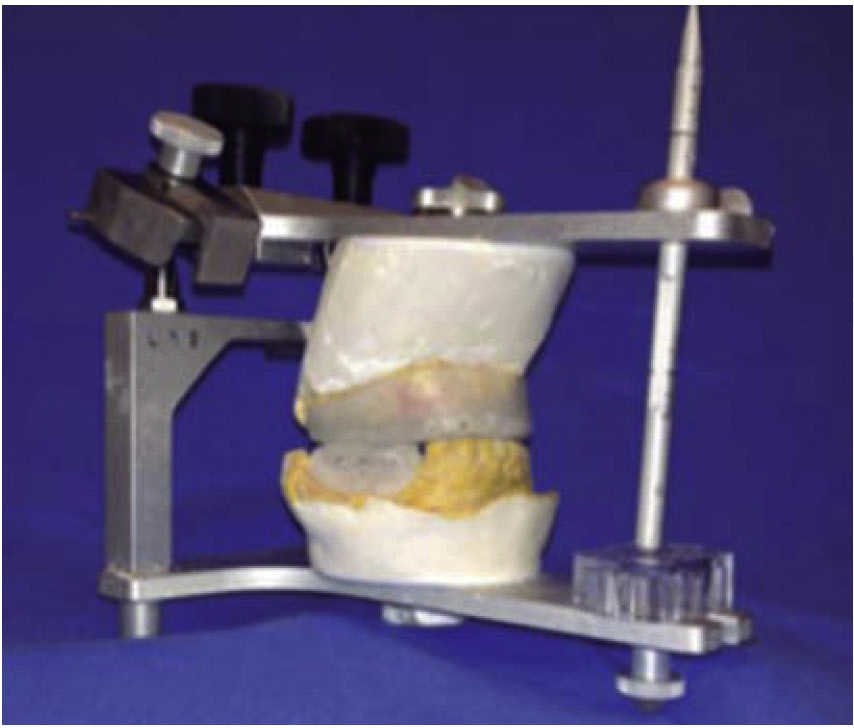

Treatment was initiated with immunization, antibiotic therapy, analgesia, extraction of septic foci and mechanical cleansing of the wound. The patient lacked removable or partial prostheses, so in order to establish inter-maxillary relationship and facial height, gunning splints were manufactured in order to establish inter-maxillary relationship (Figure 13). After ten days of initial treatment, the patient exhibited suitable alveolar healing, with presence of non-fetid secretion at the level of the mandibular wound. The second procedure was then undertaken with extra-oral approach; a 2.4 mandibular reconstruction plate and a 2.0 bone segment plate were used (Figures 14 and 15). The patient was discharged, and she attended periodic assessment visits which showed suitable healing (Figure 16) and adequate mandibular mobility. Three weeks after reconstruction, the patient was instructed to initiate prosthetic treatment in order to achieve rehabilitation.